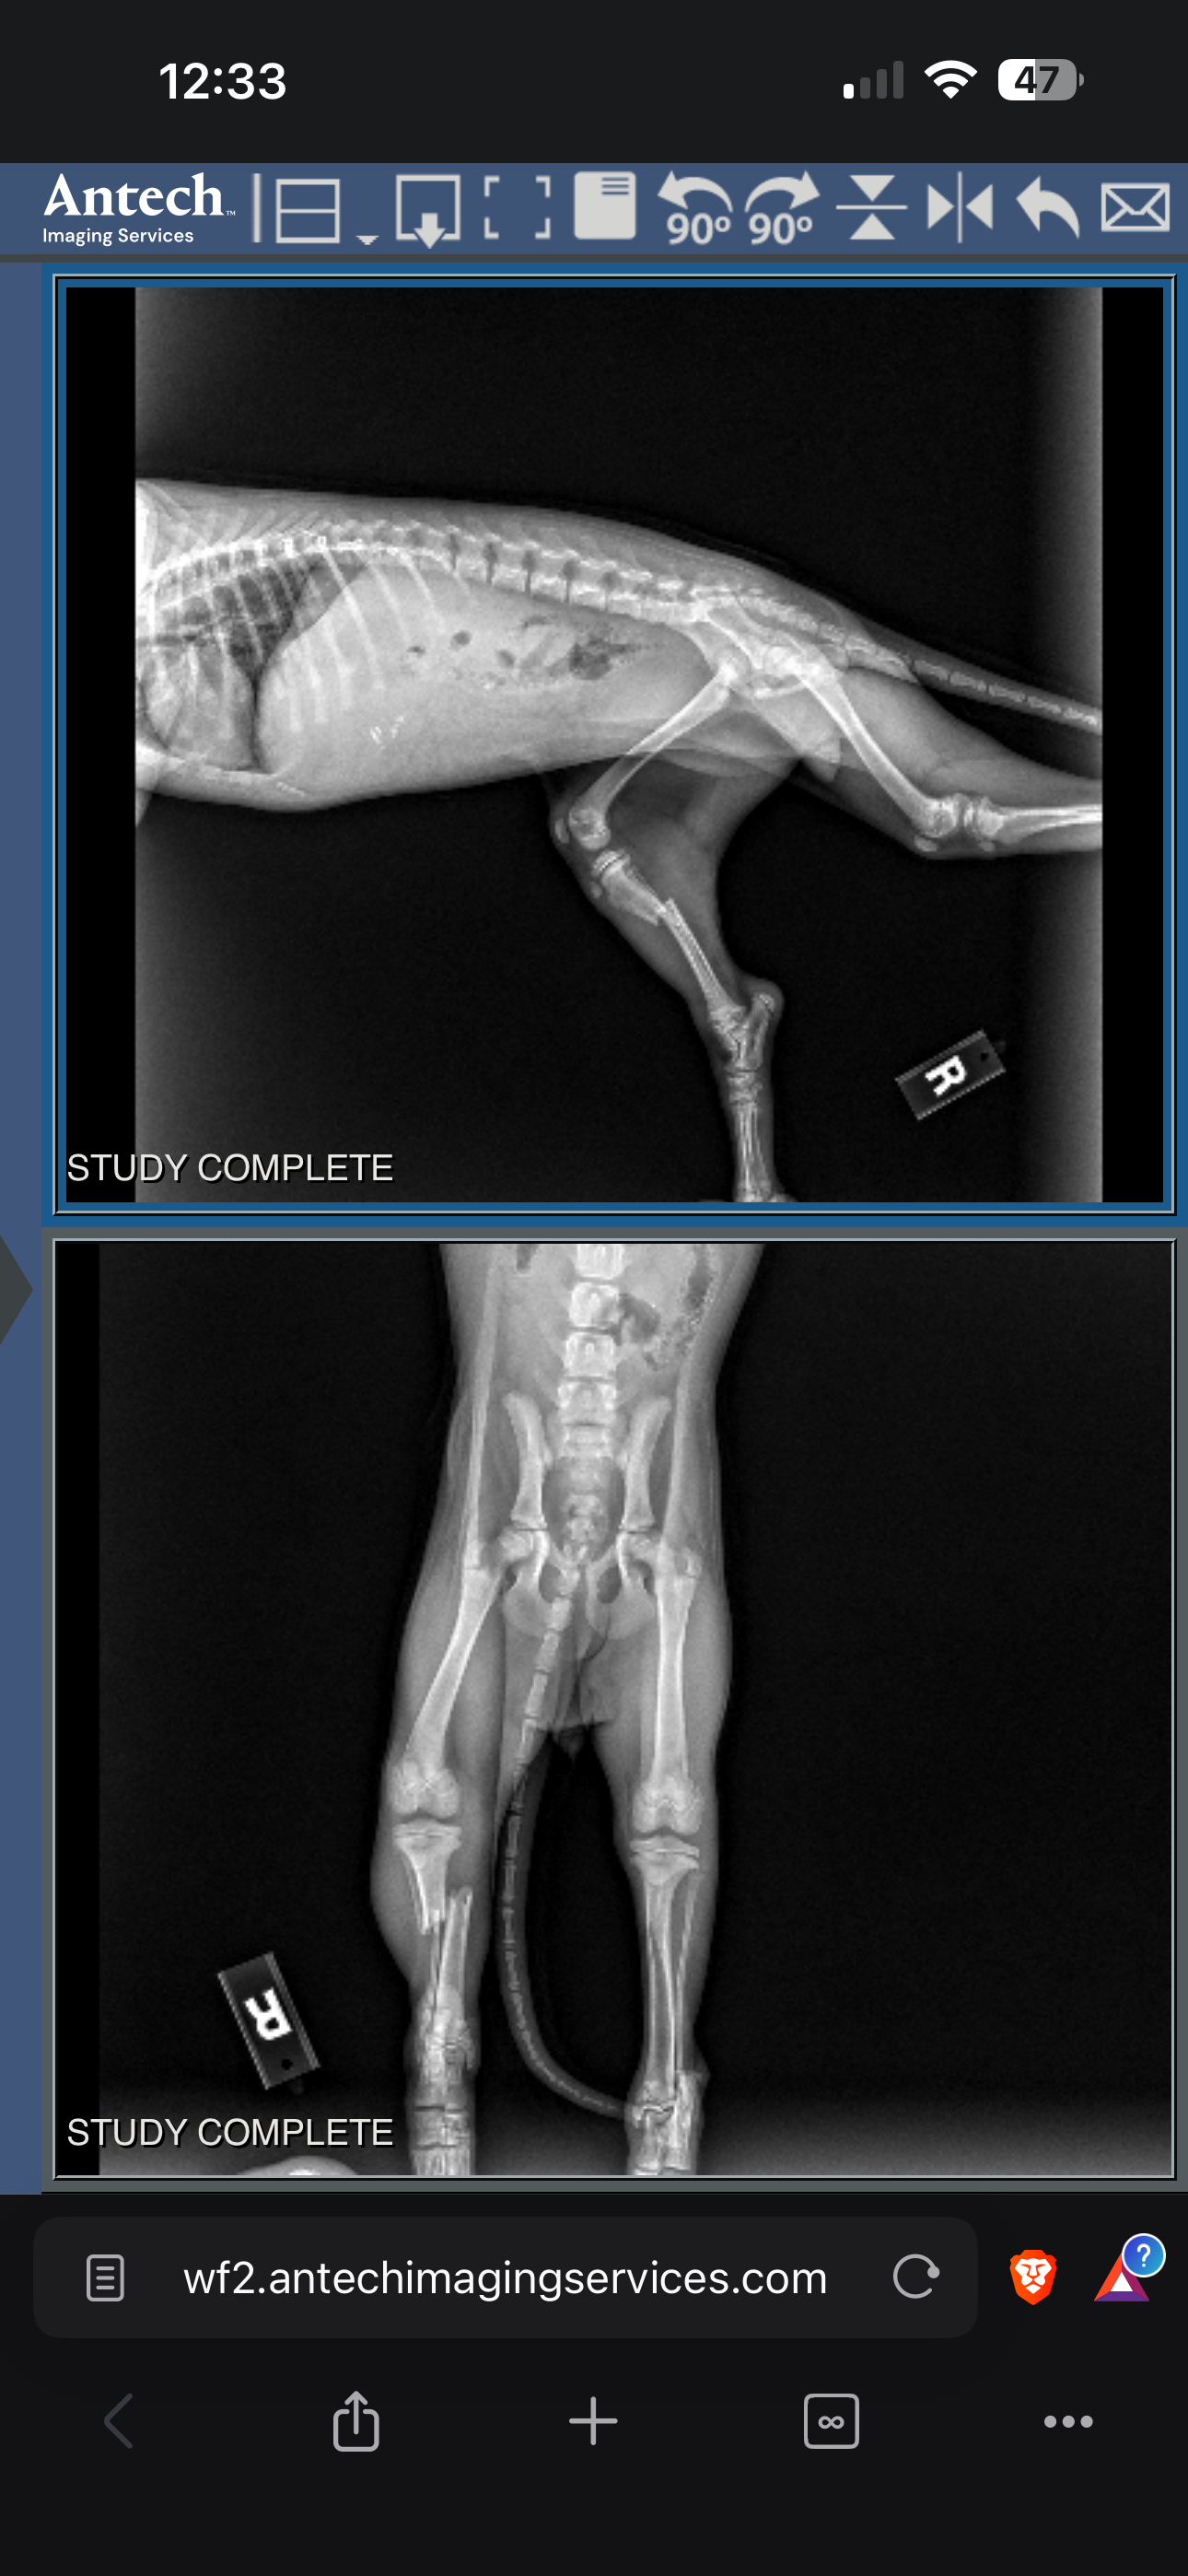

Yesterday I drove her almost 3 hours each way to VETSPR in Caguas. The X-rays are brutal: both bones between knee and ankle completely snapped.

They couldn’t operate Thursday night or Friday — surgery is now scheduled for tomorrow (Saturday). They’re waiving all boarding fees (thank you!), but instead of a simple pin they now need a plate for proper healing. Total bill: $2,100. I already paid $1,300; I owe $800 more the moment she wakes up from anesthesia.